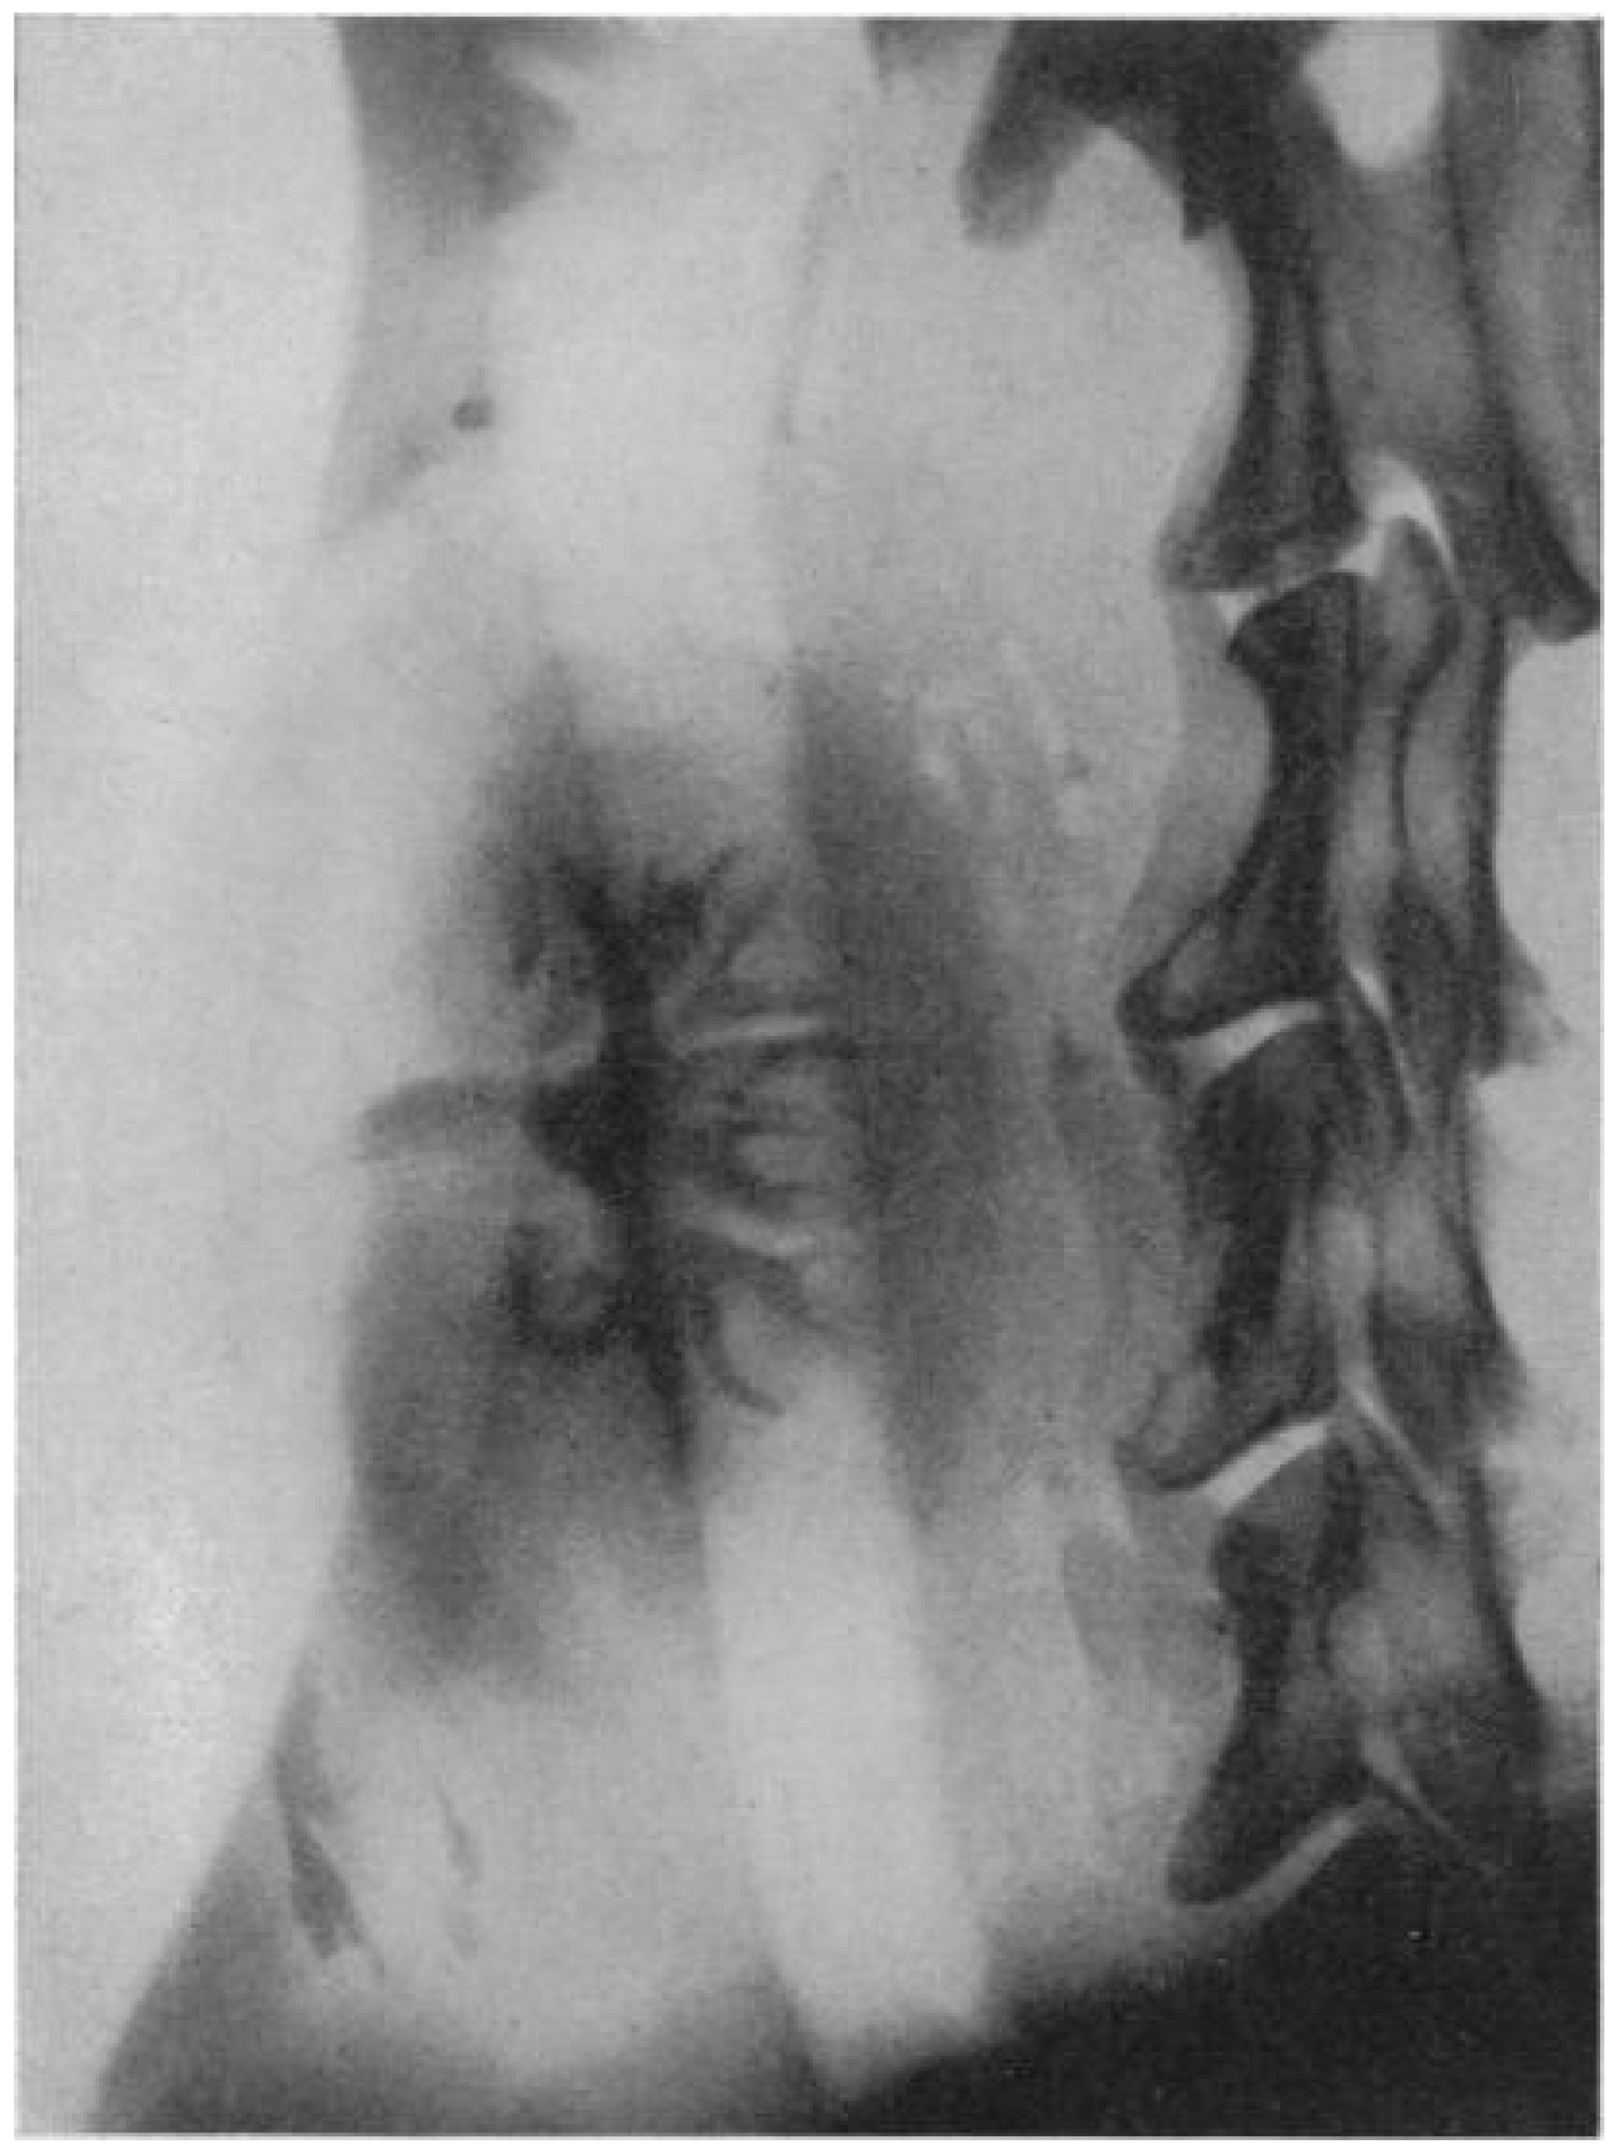

Centuries passed between the compilation of this legendary tale and the initial quest for successful kidney transplantation, started by the surgeon Emerich Ullmann in Vienna, Austria, in 1902. By performing a dog-to-dog kidney transplantation, resulting in five days of kidney transplant function, he motivated European surgeon-scientists to move forward in this medical endeavor [2]. In the same year, Alexis Carrel, a genius surgeon and a controversial political figure, published his first article on the vascular anastomosis of the jugular and carotid artery. His pioneering work on blood vessel anastomosis, as well as experimental vessel and organ transplantation, guided by his mentor Mathieu Jaboulay, is still considered the essential surgical innovation for later human-to-human transplantation. For these efforts, he was awarded the Nobel Prize in Physiology or Medicine in 1912, as the youngest physician-scientist to date [3,4,5]. The next gigantic step for organ transplantation was taken by the Ukrainian surgeon Yurii Y. Voronoy in 1933. With his surgical team from Kherson in Ukraine, he performed the first human-to-human deceased donor kidney transplantation. This surgical intervention resulted in hyperacute rejection and the death of the 26-year-old recipient just two days after transplantation, for which the recipient’s history of mercury intoxication, the extremely long warm ischemia time of more than 6 h, and blood group mismatch are considered to be the main causes [6,7]. However, the potential was recognized, and new initiatives and experiments were started. In 1950, Dempster et al. performed successful dog-to-dog transplantations, with the neck as the surgical site. This also resulted in the first available diagnostic image of the graft, an X-ray image using the injection of a 35% pyelosil contrast fluid (Figure 1) [8].

Figure 1.

The first available diagnostic image, an X-ray image at 12 min after injection of a 35% pyelosil contrast fluid, of a dog-to-dog transplanted kidney (Dempster, Ann R Coll Surg Engl. 1950) [8].

A brief description of the technique used for this experiment is as follows: “The site used has been the neck where the kidney has been interposed on the carotid–jugular circulation. At the mid-point of the carotid artery, its sheath was stripped for some millimeters, a bulldog clamp applied below and a ligature above; finally, the artery was sectioned between by a sharp razor blade. When suturing was employed, the usual Carrel technique followed; continuous over and over sutures were found satisfactory to effect an end-to-end anastomosis”.